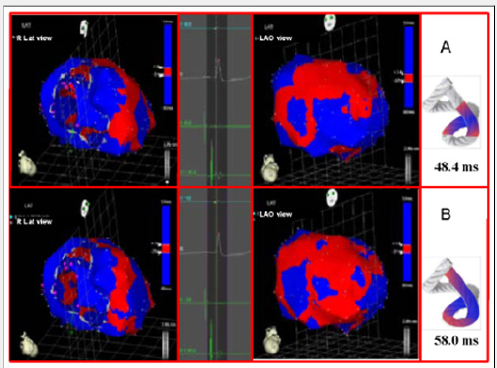

The EAM took an average of 20 minutes per patient. There were no complications Figures 3-5 illustrate endo and epicardial propagation of electrical activation. In all figures, the left panel shows the right lateral projection and the right panel the simultaneous left anterior oblique projection. The activated areas at each moment are seen in red. The lateral part represents the activation of the bands in Torrent Guasp’s rope model [1], where the depolarized zones are shown in red and previously activated zones in refractory period in blue. Below the rope can be seen the average propagation time of electrical muscle band measured in ms on the site analyzed (Table 1). This analysis was performed correlating the path of the stimulus with Torrent Guasp’s rope model of the cardiac band.

Left ventricular activation happens in the inter ventricular septum at 12.4ms±1.816ms after the start (Figure 3A). Next, following the anatomical arrangement of the descending band it spreads axially towards the ventricular apex. At that moment, the epicardial zone is also activated –the ascending band segmentevidencing radial activation in a region that can be termed as “segment intersection” (Figure 3B). It occurs on average after 25.8ms±1.483ms septal stimulation and 38.2ms±2.135 the onset of cardiac activation. This finding, as later discussed, modifies Torrent Guasp’s model and constitutes the electrical foundation of the mechanical phenomenon of ventricular twisting. Synchronously following the anatomical arrangement of the descendent band, activation moves axially towards the ventricular apex reaching the same on average of 58ms±2.0ms (Figures 4A & 4B) and (Table 1). From “segment intersection” the activation loses its unidirectional character and becomes more complex. Figure 4A shows 3 simultaneous wave fronts: 1) The distal activation of the descending band towards the apical loop; 2) the depolarization of the ascending band from the intersection towards the apex and 3) the activation of the ascending band from the intersection towards the end of the muscle band in the aorta.

Figure 4: A: Bidirectional activation of the apex and the ascending band. The final septal activation is seen propagating towards the apex, synchronously with the epicardial activation in the same direction. At the same time, the epicardial activation propagates towards the base of the left ventricle. B: Propagation progress. The activation progresses in the directions of the previous figure.